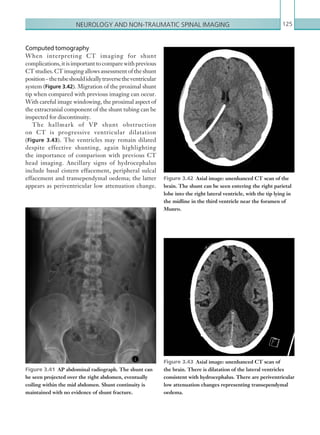

• 51.

Gastrointestinal and genitourinaryimaging 29 is more helpful in cases of occult or intermittent GI bleeding). CTA is increasingly being used as the first- line imaging modality of choice and is a useful adjunct in cases where endoscopy has failed to identify a source of bleeding. The sensitivity of CT decreases if bleeding is intermittent and timing the scan with the clinical signs of active bleeding is essential. Utilising triple- phase CTA (unenhanced, arterial and delayed phases) increases sensitivity and specificity when compared with using a single phase only. Oral contrast may mask the potential site of bleeding and should therefore be omitted. It is also important to consider whether the patient has had any recent oral contrast examinations, since this can also lead to a false-positive result. Barium enemas are of particular importance, since the oral contrast can remain in diverticulae for months or even years.Catheterangiographyisinvasiveandisnowadays lesssensitivethanCTA;assuchitisgenerallyperformed once CTA has identified a bleeding point, with an aim to embolisation and treatment. (See Table 2.3.) Radiological findings Computed tomography The GI tract should be scrutinised systematically, with careful attention being paid to the locations that are common sources of bleeding (stomach, duodenum and colon). The focus of acute GI bleeding is located by identifying high attenuation material (90 Hu) within the bowel lumen on the arterial phased scan, which represents active extravasation of IV contrast. ACUTE GASTROINTESTINAL BLEEDING Acute gastrointestinal (GI) bleeding is a medical and surgical emergency, with an associated mortality of up to 40% (Walsh et al., 1993). GI bleeding has many causes (Table 2.2) and can be divided into upper and lower tract bleeding, according to its location in relation to the ligament of Treitz. Upper tract bleeding is more common than lower tract bleeding, comprising approximately 75% of cases (Ernst et al., 1999). Symptoms such as haematemesis and melaena usually indicateanuppertractsource,whereasfreshperrectum bleeding usually signifies bleeding from the lower GI tract. Profound bleeding can result in haemodynamic instability and therefore urgent localisation of the source is vital. Endoscopy has traditionally been considered the first-line investigation for suspected GI bleeding, especially in cases of suspected upper tract bleeding. Limitations of endoscopy include an inability to visualise the upper tract distal to the fourth part of theduodenumanddifficultyinvisualisingbleedingfoci because of profound intraluminal haemorrhage. With the increasing sensitivity of CT and ease of access, radiological investigations are increasingly being considered as the first-line investigation. Radiological investigations Radiological investigations that play a part in the management of GI bleeding include CTA, catheter angiography and radionucleotide imaging (the latter UPPER LOWER Mallory–Weiss tear Angiodysplasia Oesophageal varices Diverticulitis Gastric/duodenal ulcer Colitis Gastritis Malignancy Malignancy Table 2.2  Causes of gastrointestinal bleeding. MODALITY PROTOCOL CT Unenhanced. No oral contrast. Scan from above diaphragm to femoral head level. Aortic angiogram: 100 ml IV contrast via 18G cannula, 4 ml/sec. Bolus track centred on mid-abdominal aorta. No oral contrast. Scan from above diaphragm to femoral head level. Delayed phase. IV contrast as above, scan at 120 seconds after start of contrast injection. No oral contrast. Scan from above diaphragm to femoral head level. Table 2.3 Acute gastrointestinal bleeding. Imaging protocol. K22247_C002.indd 29 16/05/15 3:07 AM

• 52.

Chapter 230 This isusually more apparent and accumulates on the delayed phase (Figures 2.7, 2.8). It is vital to scrutinise the unenhanced phase to assess for pre- existing foci of high attenuation within the bowel lumen that may lead to false positives; these can include ingested tablets, foreign bodies and suture material. Previous imaging should also be reviewed in this regard. Cone beam artefact is another common false positive, occurring at interfaces between fluid and air within the bowel. Bleeding in the distal oesophagus may be secondary to oesophageal varices, a complication of portal hypertension. These may be visualised as dilated, • Splenomegaly. • Ascites. • Varices: splenic/oesophageal. • Underlying cause (i.e. liver cirrhosis with atrophy and nodular/irregular contour). • Contrast enhancement of para-umbilical vein. Table 2.4 Computed tomographic signs of portal hypertension. Figure 2.7  Axial image: contrast enhanced CT scan of the abdomen in the arterial phase. Hyperdense material can be seen in a dependent position within the lumen of the ascending colon (arrow), consistent with an acute, arterial haemorrhage. Figure 2.8  Axial image: contrast enhanced CT scan of the abdomen in the delayed phase. On delayed imaging, further contrast has accumulated within the lumen of the ascending colon as a result of continued, active haemorrhage at this site. serpiginous enhancing vessels in the region of the distal oesophagus. Findings suggestive of liver cirrhosis and portal hypertension, such as an irregular liver outline and splenic enlargement, should prompt the search for oesophageal varices (Table 2.4; Figures 2.9, 2.10). IfGIbleedingisidentified,itisimportantto consider anunderlyingcause.Muralthickeningcanbemalignant, inflammatory, ischaemic or infective in nature, all of whichcanbecomplicatedbybleeding.Itisalsoimportant to appreciate that GI bleeding is often intermittent and it is not uncommon for CTA to be normal, even in haemodynamically compromised patients. K22247_C002.indd 30 16/05/15 3:07 AM

• 53.

Gastrointestinal and genitourinaryimaging 31 Figure 2.9a, b  Axial and coronal images: unenhanced CT scans of the abdomen. A transjugular intrahepatic portosystemic shunt (arrow) and coiled oesophageal varices are shown. Figures 2.10a–c  Axial images: unenhanced, ­arterial and delayed phase CT scans of the abdomen. This sequence of images demonstrates a contrast blush on the arterial phase within the stomach (arrow). No ­corresponding density is seen on the unenhanced scan. Findings are in keeping with acute gastric bleeding. The spleen is enlarged, ­suggestive of underlying portal hypertension. (a) ( b) (c) ( b)(a) K22247_C002.indd 31 16/05/15 3:07 AM

• 54.

Chapter 232 BOWEL PERFORATION GIperforation is an emergency condition requiring urgent surgical intervention. Clinical diagnosis of the site of bowel perforation is difficult as the symptoms may be non-specific. Diagnosis depends mostly on imaging investigations, and a correct diagnosis of the presence of, site and cause is crucial for appropriate management and for planning surgery. Breach of the GI tract wall can be due to peptic ulcer disease, inflammatory disease, blunt or penetrating trauma, iatrogenic factors, a foreign body or a neoplasm. Clinical presentation is usually that of abdominal pain and nausea and vomiting, with signs of peritonitis including rebound tenderness and guarding on palpation. Patients can be extremely unwell with signs and symptoms of shock. Inflammatory markers (C-reactive protein) and raised white cells may be present on laboratory blood analysis. Radiological investigations The first-line imaging investigations for suspected bowel perforation are plain films, including an erect CXR and a plain abdominal film, but these are only sensitive in 50–70% of cases. Contrast studies are no longer indicated in the acute setting. As well as having a suboptimal sensitivity, plain films will not demonstrate the site of perforation, which is useful to know prior to surgery. CT is the imaging modality of choice, as it provides the most information for planning surgery, with a sensitivity of 86% in identifying the site of perforation. The goal of imaging is to identify extraluminal leakage and the subsequent inflammatory reaction around the perforation site. (See Table 2.5.) Key points • CTA and catheter angiography are useful in conjunction with oesophagogastroduodenoscopy and colonoscopy in the investigation of acute GI bleeding, although the sensitivity is reduced when bleeding is intermittent. • Triple-phase CTA increases the sensitivity of detection of acute bleeding and should be performed without oral contrast. • Active bleeding appears as a high attenuation focus within the bowel lumen on the arterial phase, which becomes more pronounced on the portal venous phase. Scrutiny of the unenhanced images reduces false positives. Report checklist • Identify the bleeding vessel where possible, and the large artery of which it is a branch. • Consider underlying causes. • Look for signs of significant intravascular volume loss (e.g. flattening of the IVC). • Emphasise that bleeding can be intermittent and therefore a ‘normal’ scan does not exclude GI bleeding. • Recommend urgent interventional radiology referral. References Ernst AA, Haynes ML, Nick TG et al. (1999) Usefulness of the blood urea nitrogen/creatinine ratio in gastrointestinal bleeding. Am J Emerg Med 17:70–72. Walsh RM, Anain P, Geisinger M et al. (1993) Role of angiography and embolization of massive gastroduodenal haemorrhage. J Gastrointest Surg 3:61–65. MODALITY PROTOCOL Plain film imaging AP supine abdominal radiograph to include the liver. A left lateral decubitus film can be performed with the patient lying on their left and the right side up. Erect chest radiograph to include the diaphragms. Patient should be upright for at least 10 minutes prior to image acquisition. CT Post IV contrast, portal venous phase: 100 ml IV contrast, 4 ml/sec via 18G cannula. Scan at 70 ­seconds. Scan from above diaphragm to femoral head level. Table 2.5 Bowel perforation. Imaging protocol. K22247_C002.indd 32 16/05/15 3:07 AM

• 55.

Gastrointestinal and genitourinaryimaging 33 Radiological findings Plain films The presence of free air under the diaphragm on an erect chest plain film is diagnostic of free intraperitoneal air (Figure 2.11). As little as 1 ml of air can be identified under the diaphragm. Care should be taken not to confuse the stomach bubble under the left hemidiaphragm with free air. Aplainabdominalfilmcanrevealabowelperforation, with the presence of Rigler’s sign (gas outlining both sides of the bowel wall) (Figure 2.12). Other abdominal plain film signs of free air include football sign (oval- shaped peritoneal gas), which is more common in children (Figure 2.13), increased lucency over the right upper quadrant (gas accumulating anterior to the liver) or the triangle sign (gas accumulating between three loops of bowel). Free gas can also be seen outlining ligaments in the abdomen, such as the falciform ligament (Figure 2.14). A left lateral decubitus film can also be used in the detection of small amounts of free air that may be interposed between the free edge of the liver and the lateral wall of the peritoneal cavity. Figure 2.11  AP semi-erect chest radiograph. Large volumes of gas can be seen underneath the diaphragm consistent with pneumoperitoneum. Figure 2.13  AP supine abdominal radiograph. A large, rounded lucency is seen projected in the ­mid-­abdomen representing free intra-abdominal gas in a ­non-dependent location. The falciform ligament is also seen outlined clearly by free gas (arrow). Figure 2.12  AP supine abdominal radiograph. Gas can be seen within the peritoneum on both sides of the bowel wall (Riggler’s sign), highlighting multiple loops of dilated small bowel. K22247_C002.indd 33 16/05/15 3:07 AM

• 56.